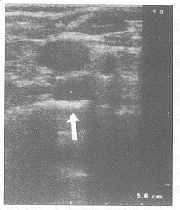

2.2 无回声型 此类淋巴结核声像图类似囊肿,表现为散在的或互相融合成蜂窝状的无回声,无回声内可有散在的光点样回声,后方可伴有回声增强效应。见图1。

图1 ↑示淋巴结核呈无回声型,类似囊肿,后方透声增强